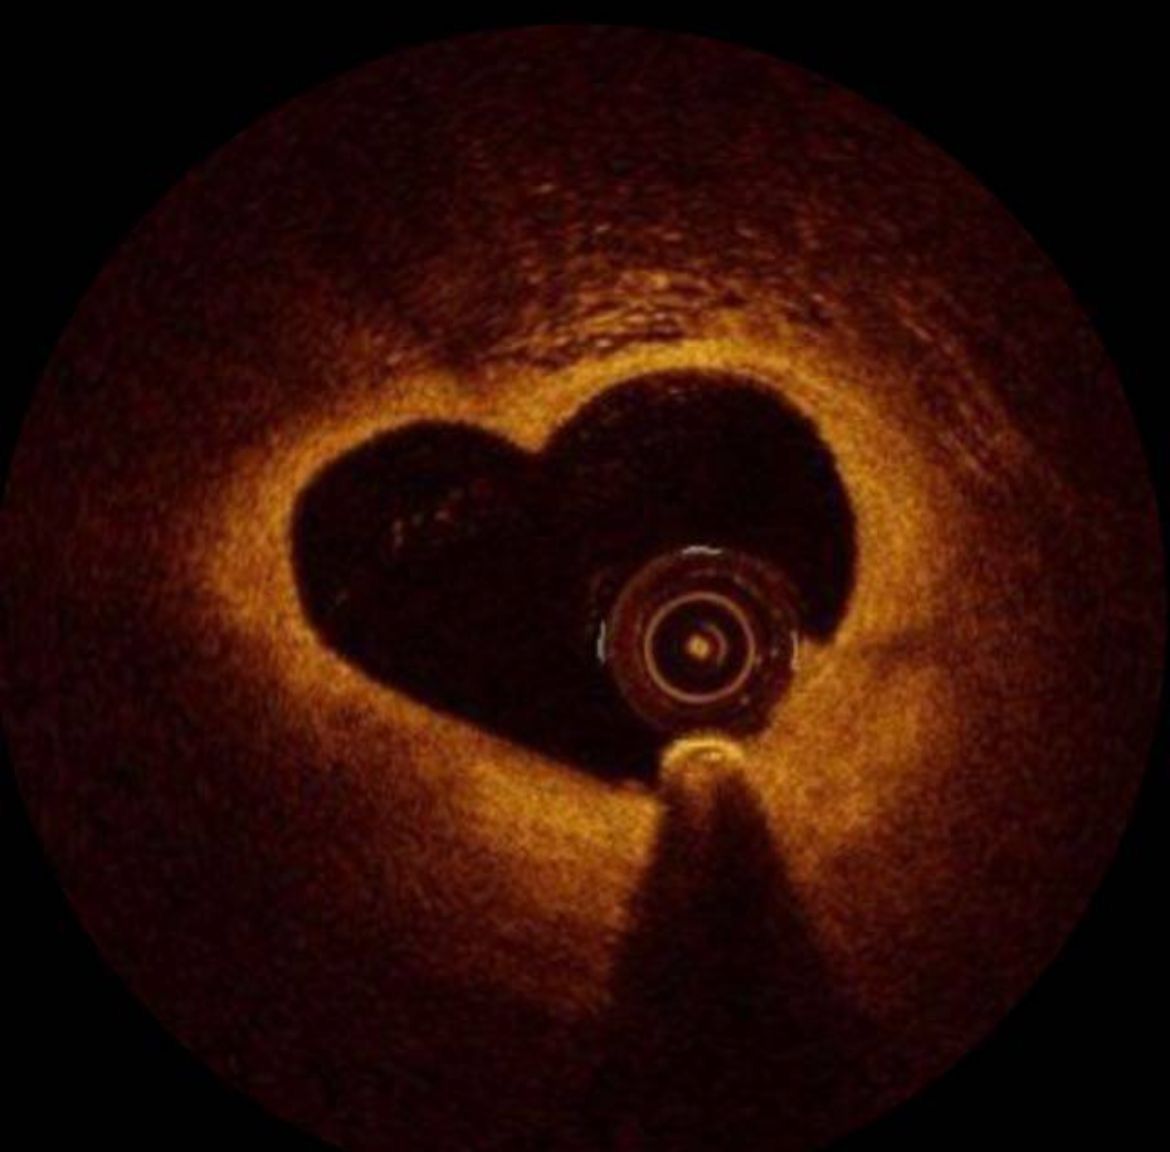

Ad oggi, ha eseguito più di 4000 coronarografie ed oltre 1800 angioplastiche coronariche con impianto di stent come primo operatore e partecipa all'attività interventistica strutturale. Negli anni si è dedicato alla ricerca scientifica pubblicando su prestigiose riviste scientifiche internazionali, collaborando in registri nazionali ed internazionali ed in Trial clinici randomizzati. Tale ricerca si è rivolta all'approfondimento dell'uso delle moderne tecniche di imaging coronarico (IVUS, OCT) per la valutazione dell'aterosclerosi vulnerabile, per l'ottimizzazione delle procedure ad alta complessità (malattia del tronco comune, coronaropatia multivasale, biforcazioni, dissezione coronariche spontanee), alle tecniche di studio della fisiologia coronarica (FFR, iFR) ed allo studio non invasivo dell'anatomia coronarica (TAC coronarie).